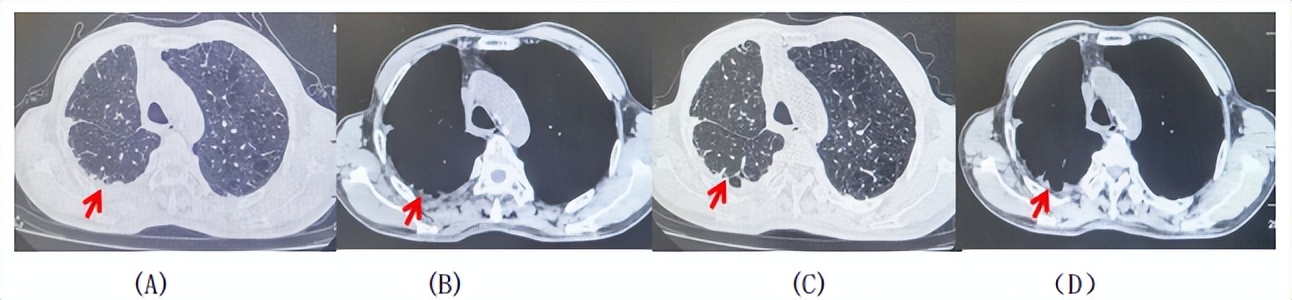

2024.11.19患者出现右侧胸痛,复查胸部CT检查示右侧胸膜肿物,大小约31mmX24mm,右侧4、5肋骨骨质破坏,考虑转移(如图2)。建议患者穿刺活检取病理明确诊断,患者拒绝,经MDT会诊后结合影像学表现及病史考虑为胸膜转移,肋骨转移,分期为rT0N0M1a IVA期,DFS仅仅17个月。2024.12.05起行信迪利单抗联合培美曲塞+卡铂方案治疗4周期,复查胸CT评效PR(如图3)。之后给予信迪利单抗+培美曲塞维持治疗6周期,期间复查CT评效PR(如图3)。目前信迪利单抗+培美曲塞维持治疗中,截止至目前PFS约为8个月,治疗期间未出现明显毒副反应。

图3:患者免疫联合化疗治疗后胸部CT,(A、B)图展示信迪利单抗联合培美曲塞+卡铂治疗

4周期(2025.02)疗效,(C、D)图展示信迪利单抗+培美曲塞维持治疗6周期(2025.07)疗效